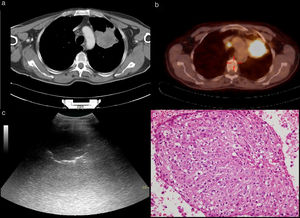

There were 79 (76%) patients in the US-TFNAB diagnostic group and 25 (24%) in the US-TFNAB non-diagnostic group. When the final diagnostic methods of these 25 patients (US-TFNAB non-diagnostic group) were examined, it was observed that 13 (52%) patients’ final diagnosis was achieved using CT-guided Tru-cut biopsies, 9 (36%) with fiberoptic bronchoscopy (FOB), and 3 (12%) with thoracic US-guided Tru-cut biopsies. The distribution of the final histopathologic diagnoses of the patients is given in Table 3. The mean number of TFNABs per patient was 1.09 ± 0.28.When the PET-CT reports of the patients were examined, the mean SUVmax in PET-CT scans was 19.5 ± 10.1 in the US-TFNAB diagnostic group, whereas it was 15.1 ± 8.9 in the US-TFNAB non-diagnostic group (p = 0.016) (Fig. 2). When heterogeneous FDG uptake and homogeneous FDG uptake characteristics in PET-CT of biopsied mass lesions of the patients were examined, heterogeneous FDG uptake was reported in 41 (5) patients in the US-TFNAB diagnostic group and in 16 (64%) patients in the US-TFNAB non-diagnostic group (Figs. 2a–d) (Figs. 3a–d). There was no statistically significant relationship between lesions showing homogeneous or heterogeneous FDG uptake and the diagnostic success of the US guided-TFNAB procedure (p = 0.289) (Table 2).

a) An approximately 15 × 10-cm mass in the right lung in thoracic CT. b) Heterogeneous FDG uptake with observed necrotic areas inside the mass in PET-CT. c) Anechoic necrotic foci in the ultrasonographic image of the same mass. d) Necrotic tissue specimen (HEx200) whose structural and cellular details cannot be evaluated in the histopathologic preparation.